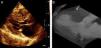

Na Figura 1 compara-se a obstrução da câmara de saída do ventrículo esquerdo (CSVE) por ecocardiografia (A) e TC (B), sendo ainda identificada uma septal (seta).